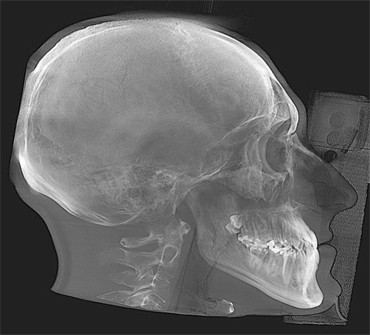

L’Unità Operativa di Radiologia Odontoiatrica, ubicata presso il Dipartimento, è dotata di apparecchiature all’avanguardia nella diagnostica odontostomatologica e del massiccio-facciale. In particolare è presente un’apparecchiatura TC Cone Beam di ultima generazione che consente l’acquisizione volumetrica ad alta definizione ed a bassissima dose dell’intero volume cranio-facciale comprese le articolazioni temporo- mandibolari e le prime vertebre cervicali. Tale esame oggi trova larga applicazione nel campo della diagnostica odontoiatrica e del massiccio facciale, come lo studio pre e post-implantare, la valutazione di elementi dentali inclusi, lo studio di lesioni odontogene e non odontogene, la traumatologia cranio-facciale ed anche la valutazione dei seni paranasali, dell’orecchio e delle articolazioni temporo-mandibolari. Grazie all’acquisizione volumetrica ed alla bassa dose di radiazioni tale metodica è oggi indicata anche nella pianificazione del trattamento ortodontico. Nell’Unità Operativa è inoltre presente l’Orthophos Plus della Sirona Dental System che consente di effettuare esami radiografici standard digitali delle arcate dentarie, dei seni paranasali e delle articolazioni temporomandibolari ed inoltre teleradiografie nelle proiezioni latero-laterale ed antero-posteriore per studio ortodontico. L’Unità Operativa è collegata in rete con i vari reparti della clinica per una rapida consultazione degli esami radiologici.